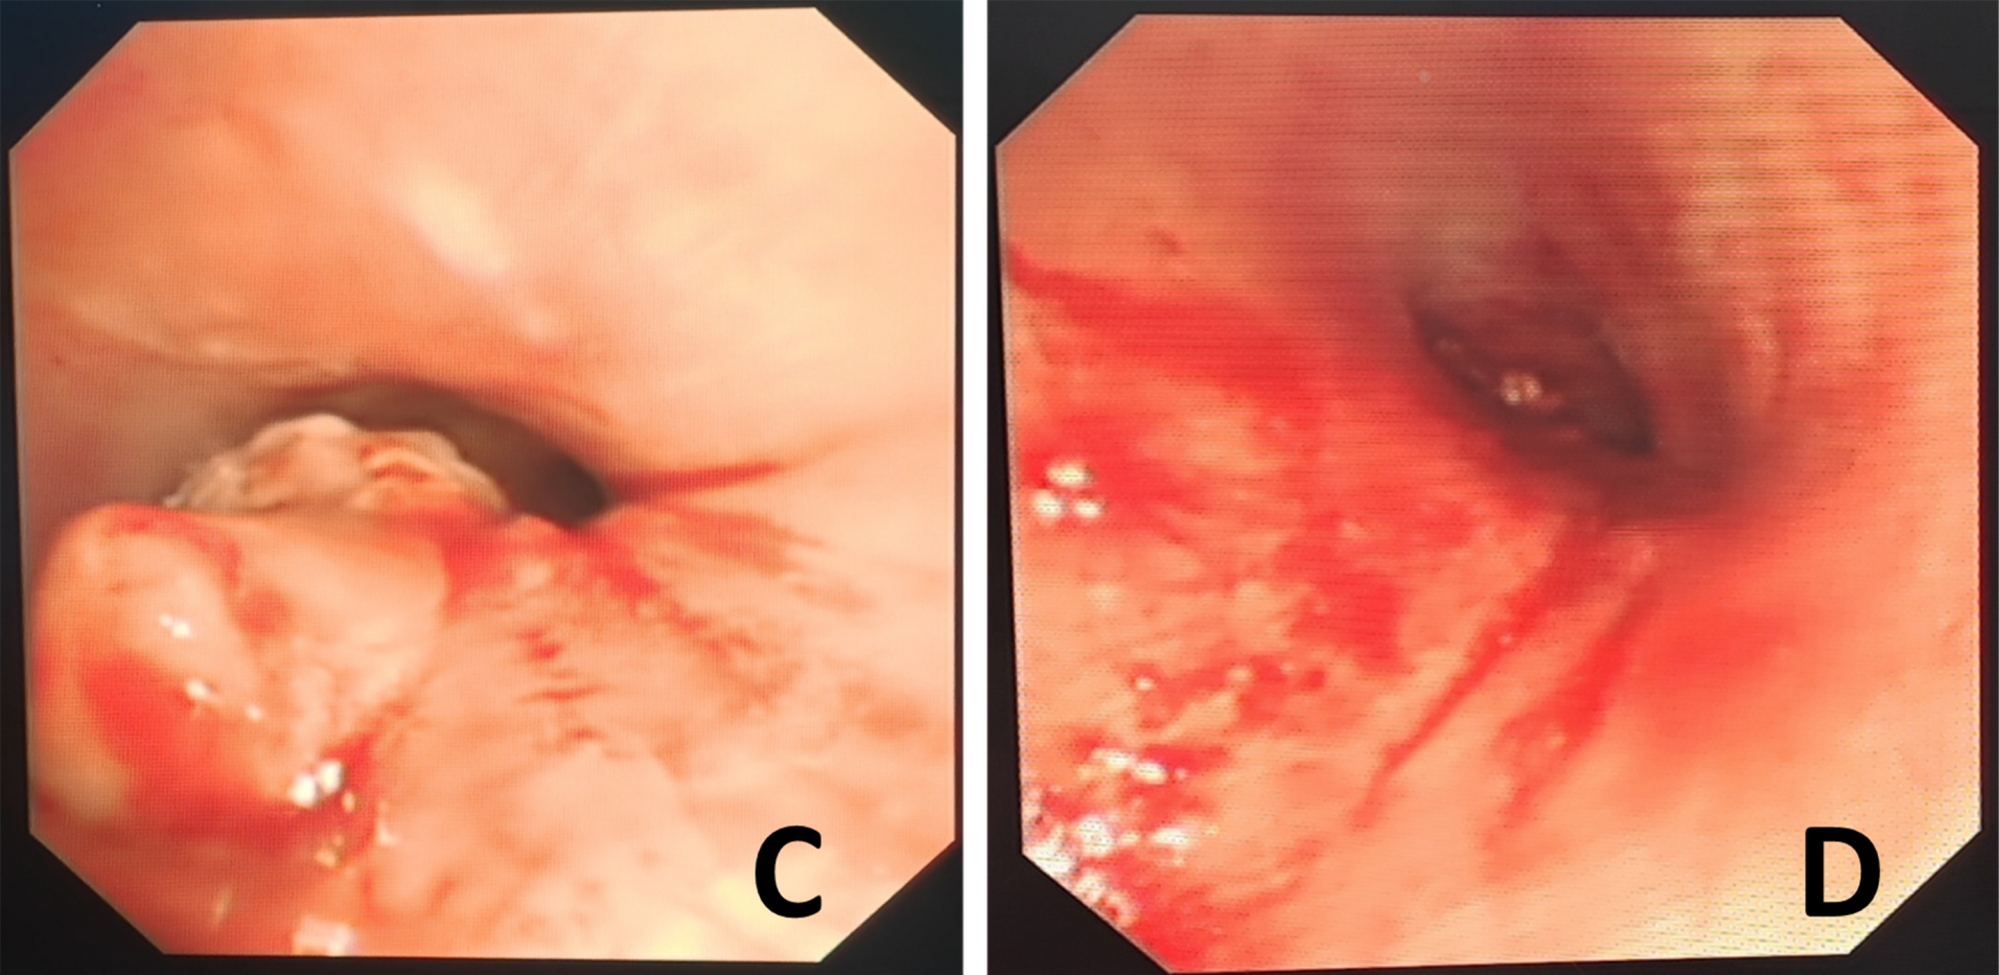

1月4日早晨8点,手术室准备就绪。除了常规手术器械,还特别准备了多种型号的气管支架、不同直径的硬质气管镜、冷冻治疗系统、氩等离子体凝固设备——这是一台需要“Plan B、C、D”的手术。麻醉开始,硬质气管镜置入,当镜体通过声门进入主气管时,内镜显示屏上的景象令人屏息:粉红色肿瘤组织几乎完全堵塞管腔,表面血管网密布,仅存的气管缝隙随着呼吸微弱开合(图2:C)。季翔副主任医师、胡海洋副主任医师和高明霞主管护师密切合作,在直径不到5毫米的狭小的操作通道内,将探头尖端精准抵近肿瘤表面。踩下脚踏板,-80℃的低温瞬间传递,肿瘤组织表面结出白色霜花。每一次冻融循环后,用抓钳取出坏死组织,如同在悬崖边上清理落石,既要彻底,又要避免损伤正常气管壁。

▲图2:硬质气管镜介入治疗前后对比

(C:治疗前,气管重度狭窄;D:治疗后,气管通畅)